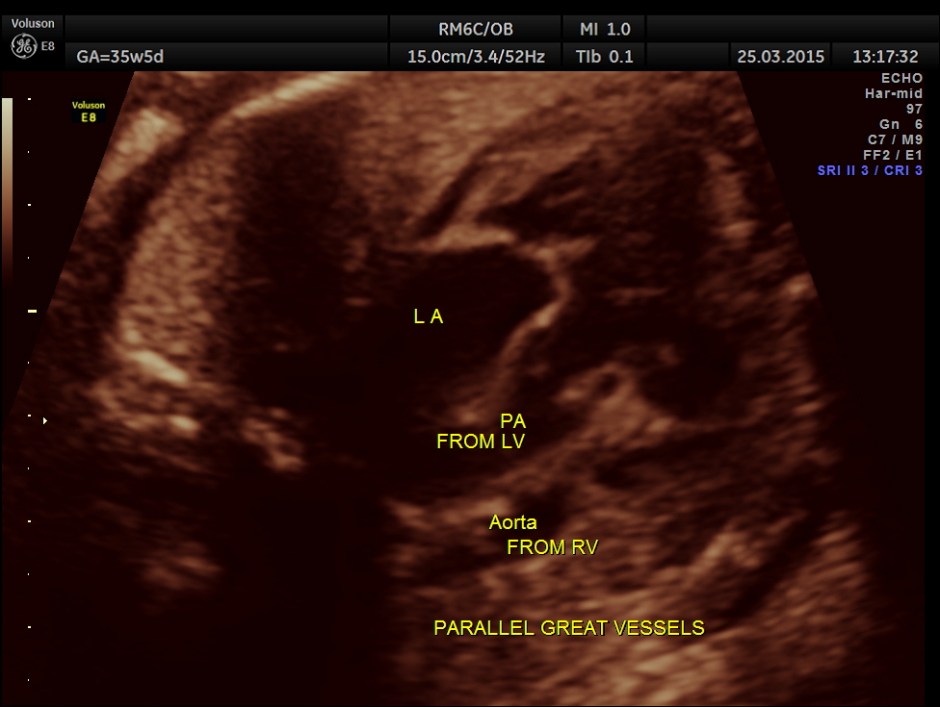

The great vessel arising from the right ventricle instead of crossing runs parallel to the vessel arising from the LV.

The great artery arising from the hypoplastic right ventricle runs parallel to the artery arising from the left ventricle.